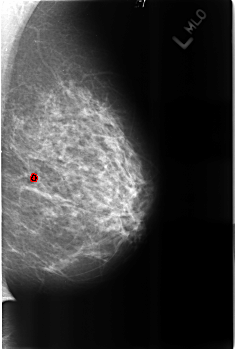

B_3222_1.LEFT_MLO

LEFT_MLO LINES 4528 PIXELS_PER_LINE 3048 BITS_PER_PIXEL 12 RESOLUTION 50 OVERLAY

FILE: B_3222_1.LEFT_MLO.OVERLAY

TOTAL_ABNORMALITIES 1

ABNORMALITY 1

LESION_TYPE CALCIFICATION TYPE LUCENT_CENTER DISTRIBUTION N/A

ASSESSMENT 2

SUBTLETY 3

PATHOLOGY BENIGN_WITHOUT_CALLBACK

TOTAL_OUTLINES 1

BOUNDARY